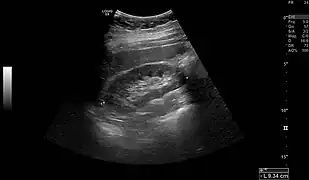

Normal adult right kidney as seen on abdominal ultrasound with a pole to pole measurement of 9.34 cm

Renal ultrasonography is essential in the diagnosis and management of kidney-related diseases.[44] Other modalities, such as CT and MRI, should always be considered as supplementary imaging modalities in the assessment of renal disease.[44]